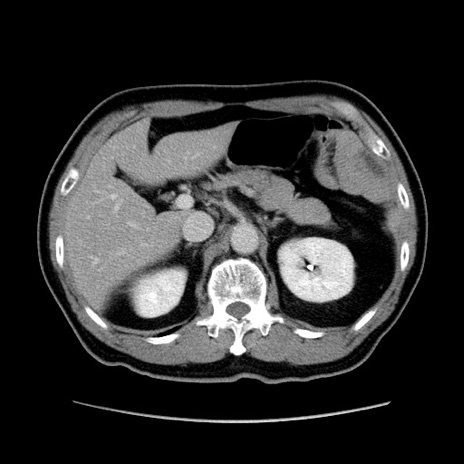

症例34(横断像)

【症例】60歳代 男性

【主訴】右鼠径部膨隆

【現病歴】1年程前より右鼠径部膨隆あり。自己にて還納可能だったため放置していた。3時間前より右鼠径部の脱出を認め、還納困難となり受診。

【身体所見】右鼠径部に小児頭大の膨隆あり。弾性硬であり、用手還納は困難。左鼠径部にも膨隆を認める。脱出はなし。

【データ】WBC 15500、CRP 測定なし